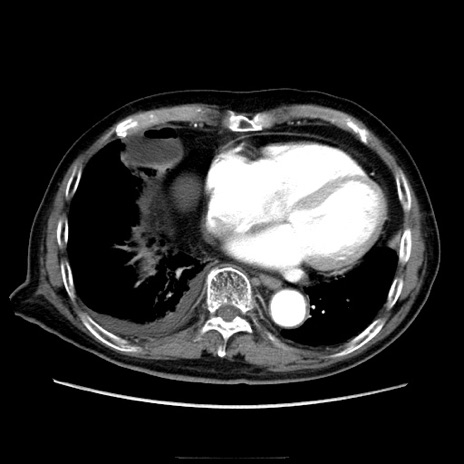

症例21(横断像)

【症例】70歳代男性

【主訴】腹痛

【現病歴】肝硬変・肝細胞癌にてかかりつけの方。約9時間前に食後より腹痛出現。症状が徐々に増悪し、嘔吐出現したため来院。

【既往歴】肝硬変、肝細胞癌(RFA、TACE後)

【身体所見】意識清明、表情苦悶様、BT 36℃、BP 129/78mmHg、P 88bpm、SpO2 97%(RA)、右上腹部から心窩部にかけて圧痛あり、反跳痛なし、筋性防御あり。

【データ】WBC 5800、CRP 0.16